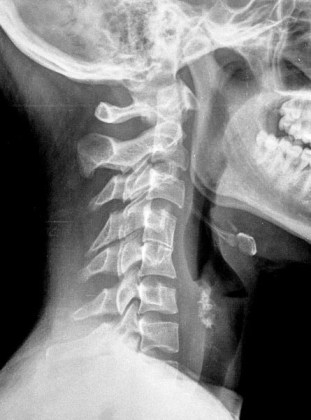

SIGNO DEL SURCO FEMORAL LATERAL

Signo indirecto de rotura del ligamento cruzado anterior (LCA) en la radiografía simple. Se trata de una depresión anormalmente profunda del surco cóndilo-patelar lateral o surco femoral lateral (flecha). Este surco es una pequeña depresión normal en la superficie articular del cóndilo, entre la curvatura que articula con la rótula y la que gira sobre la tibia. El surco anormalmente profundo se produce en la fractura osteocondral impactada, que acontece al tiempo que la rotura del LCA, ya que el mecanismo de ambas lesiones es el mismo: rotación de la articulación y valgo forzado, en el que chocan el platillo tibial contra el cóndilo femoral.

Imágenes de resonancia magnética de la rodilla, que muestran cortes sagitales de una secuencia potenciada en T1. La fotografía de la izquierda muestra como el surco femoral lateral es anormalmente profundo y se acompaña de una disminución de la señal del hueso adyacente por edema medular (flecha blanca). A la derecha, corte en el que debería verse el LCA, ausente por rotura.